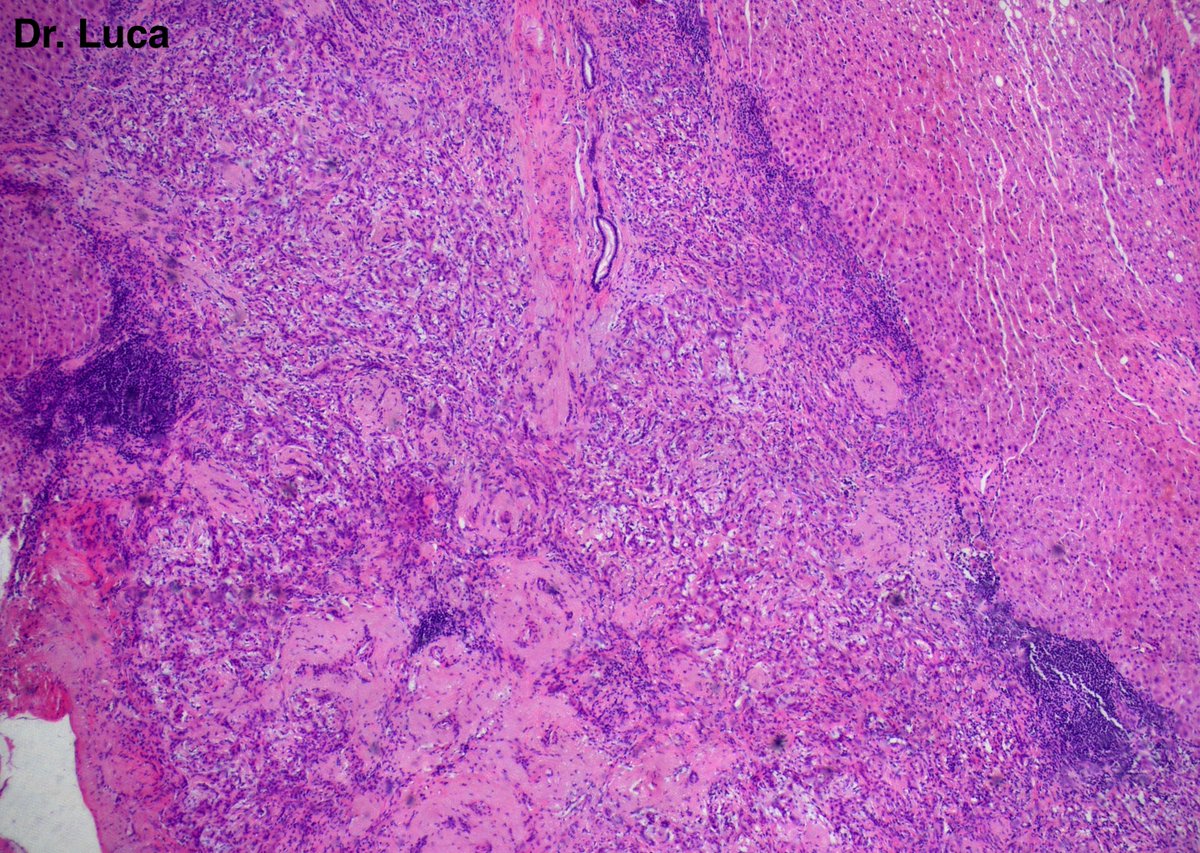

71yoM, bone metastasis, what's your quick H&E diagnosis? (no IHC) @AkgulMd @JPintoPath @slusagar @EKoubaMD @Pathmath1 @s_prendeville @goziemnweke @SumantaDas_7 @D4L14H @PoloniaAntonio @kriyer68 @md_kyle @kis_lorand @MarcosLepeMD @ivanaspath @pathobot #Pathology #PathTwitter

22

25

63